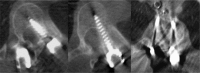

Background: Technological advances, including navigation, have been made to improve safety and accuracy of pedicle screw fixation. We evaluated the accuracy of the virtual screw placement (Stealth projection) compared to actual screw placement (intra-operative O-Arm) and examined for differences based on the distance from the reference frame.

Methods: A retrospective evaluation of prospectively collected data was conducted from January 2013 to September 2013. We evaluated thoracic and lumbosacral pedicle screws placed using intraoperative O-arm and Stealth navigation by obtaining virtual screw projections and intraoperative O-arm images after screw placement. The screw trajectory angle to the midsagittal line and superior endplate was compared in the axial and sagittal views, respectively. Percent error and paired t-test statistics were then performed.

Results: Thirty-one patients with 240 pedicle screws were analyzed. The mean angular difference between the virtual and actual image in all screws was 2.17° ± 2.20° on axial images and 2.16° ± 2.24° on sagittal images. There was excellent agreement between actual and virtual pedicle screw trajectories in the axial and sagittal plane with ICC = 0.99 (95%CI: 0.992-0.995) (p<0.001) and ICC= 0.81 (95%CI: 0.759-0.855) (p<0.001) respectively. When comparing thoracic and lumbar screws, there was a significant difference in the sagittal angulation between the two distributions. No statistical differences were found distance from the reference frame.

Conclusion: The virtual projection view is clinically accurate compared to the actual placement on intra-operative CT in both the axial and sagittal views. There is slight imprecision (~2°) in the axial and sagittal planes and a minor difference in the sagittal thoracic and lumbar angulation, although these did not affect clinical outcomes. In general, we find that pedicle screw placement using intraoperative cone beam CT and navigation to be accurate and reliable, and as such have made it a routine part of our spine practice. This study was approved by the University of Minnesota IRB (#1303E30544).